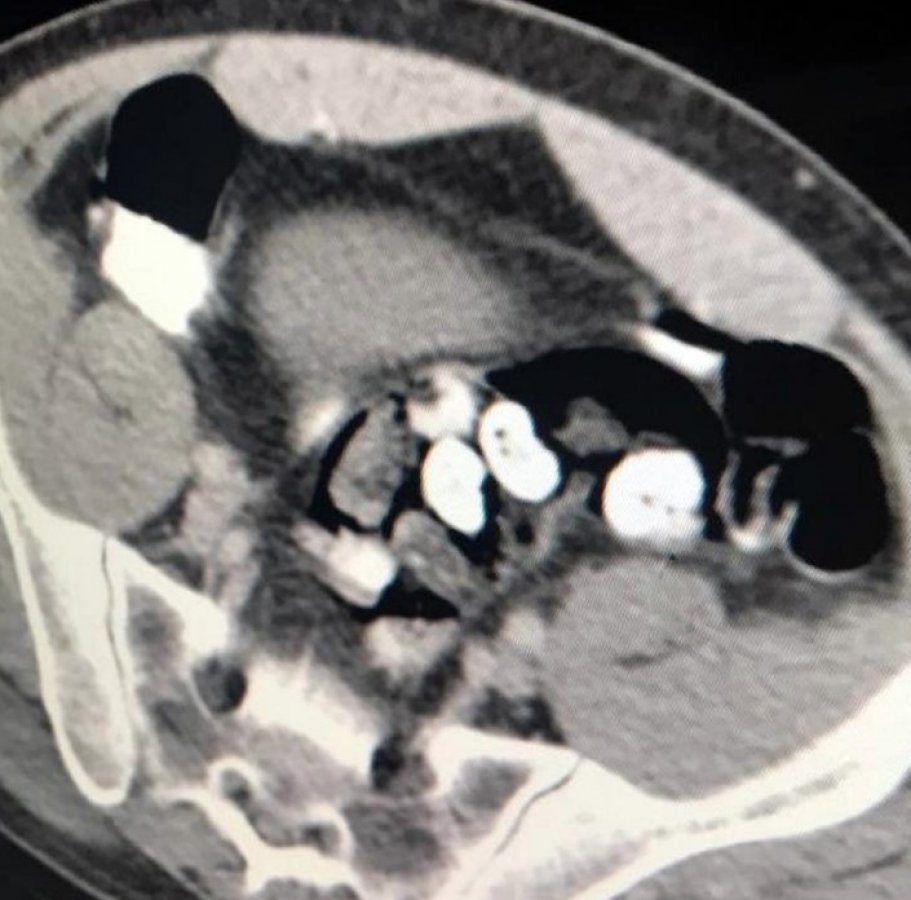

Polis bunun üzerine savcılıktan alınan izinle zanlıyı, Çukurova Üniversitesi Tıp Fakültesi Balcalı Hastanesi Gastroenteroloji Bölümüne götürdü. Burada zanlının bağırsak tomografisi çekildi. Bağırsaklarında serçe parmağı büyüklüğünde yabancı cisimler olduğu tespit edilmesine rağmen zanlı, uyuşturucu olmadığını söylemeye devam etti.